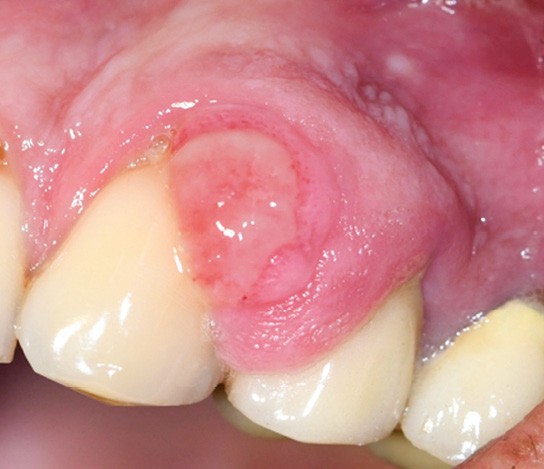

3. Épulis fibroblastique ulcéré calcifiant/ossifiant également appelé fibrome ossifiant périphérique.

- Lésion souvent ulcérée, présentant un risque de récidive (fig. 3a et b).